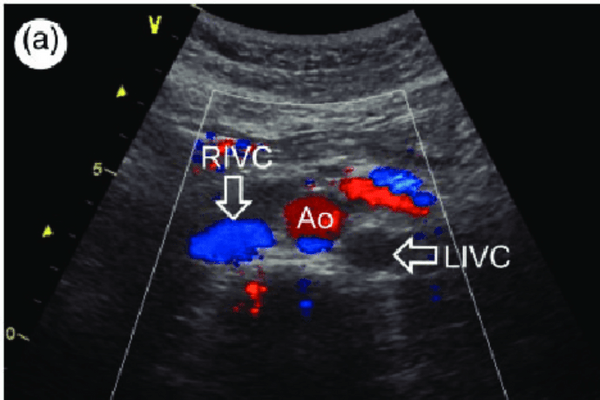

Colour Doppler is a non-invasive imaging test that uses ultrasound waves to visualize blood flow through the arteries and veins in the body. It is a painless and safe procedure that provides valuable information about the circulatory system’s function and the organs’ blood supply. The test is usually performed to diagnose conditions such as blood clots, aneurysms, and other vascular diseases.